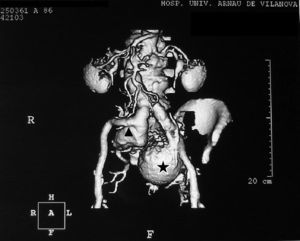

La radiografía de tórax no permitió detectar signos de insuficiencia cardíaca ni cardiomegalia. El electrocardiograma mostró ritmo sinusal a 72lpm, sin criterios de crecimiento ventricular. Las pruebas analíticas realizadas, incluyendo la de función renal, fueron normales. Se practicó una eco-Doppler abdominal y de miembros inferiores, que demostró permeabilidad del sistema venoso, con ausencia de trombosis venosa profunda asociada. Se observó la presencia de aneurisma en ambas arterias ilíacas internas (derecha: 6cm, izquierda: 9cm), sin evidencia de rotura aguda. La aorta era de calibre normal (fig. 1). La tomografía axial computarizada (TAC) realizada confirmó los hallazgos de la eco-Doppler (fig. 2).

Tras valoración en sesión medicoquirúrgica, se decidió realizar tratamiento intravascular mediante endoprótesis aortobiilíaca (Excluder-Gore®) de 26×12×16mm, más extensión ilíaca contralateral de 12×14mm, previa embolización, mediante coils, de ambos aneurismas.